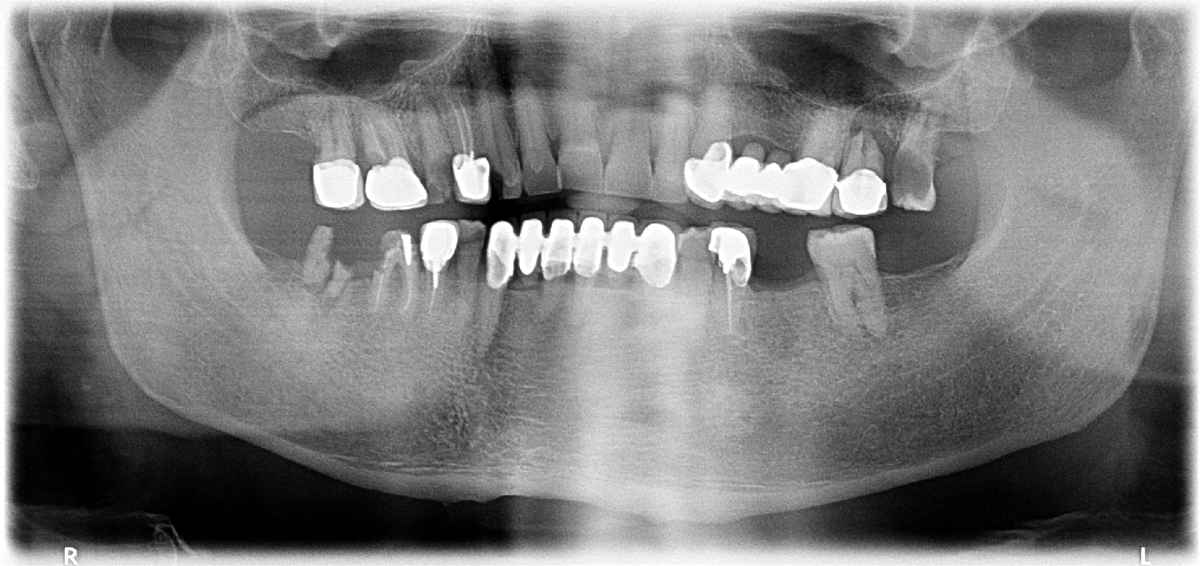

Lo studio del Dottor Vitanza si è rivelato una scelta eccellente. Un'ortopanoramica per cominciare e gran professionalità nell'analisi delle soluzioni. Grazie Dottore.

Avevo un problema che pensavo irrisolvibile invece in pochissimo tempo grazie all’innesto degli impianti eseguito dal dott. Vitanza ho ritrovato quella serenità mia sperata. Consiglio assolutamente il dott. Vitanza per la sua estrema professionalità oltre che cordialità. Lo studio è molto confortevole a davvero in ottima posizione. Tutta l'equipe merita un grande riconoscimento. Grazie ancora a presto